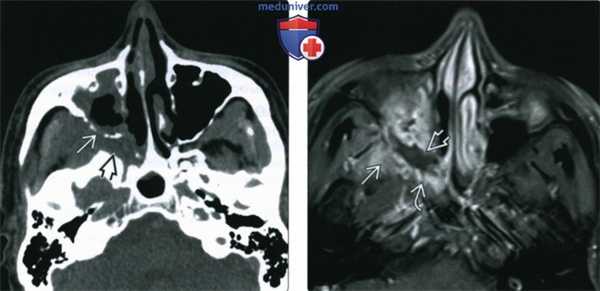

(Слева) При аксиальной КТ без КУ у пациента с диабетом и мукормикозом (ОИГРС) определяется циркулярное поражение правой верхнечелюстной пазухи с выраженными эрозиями задней стенки и замещением жировой клетчатки ретроантральной области и крылонебной ямки мягкотканным компонентом.

(Справа) При аксиальной МРТ Т1 С+ FS визуализируются фокальные неконтрастирующи-еся зоны в слизистой оболочке верхнечелюстной пазухи, соотносящиеся с некротическим струпом, жировая клетчатка ретро-антральной области и крылонебной ямки замещена мягкотканный компонентом.

(Слева) При корональной КТ без КУ у пациента с диабетом, почечной недостаточностью, жалобами на боль в глазу определяется снижение пневматизации левой верхнечелюстной пазухи, ячеек решетчатой кости с выраженным эктра- и интракональным ретроорбитальным мягкотканным компонентом, окружающим и смещающим внутреннюю и нижнюю прямые мышцы.

(Справа) При аксиальной МРТ Т1 определяется поражение решетчатой пазухи с чрескостным распространением в ретрорбитальные мягкие ткани. Была выполнена экзентерация орбиты, максиллэктомия, этмоидэктомия, подтвердился ОИГРС (Mucor).